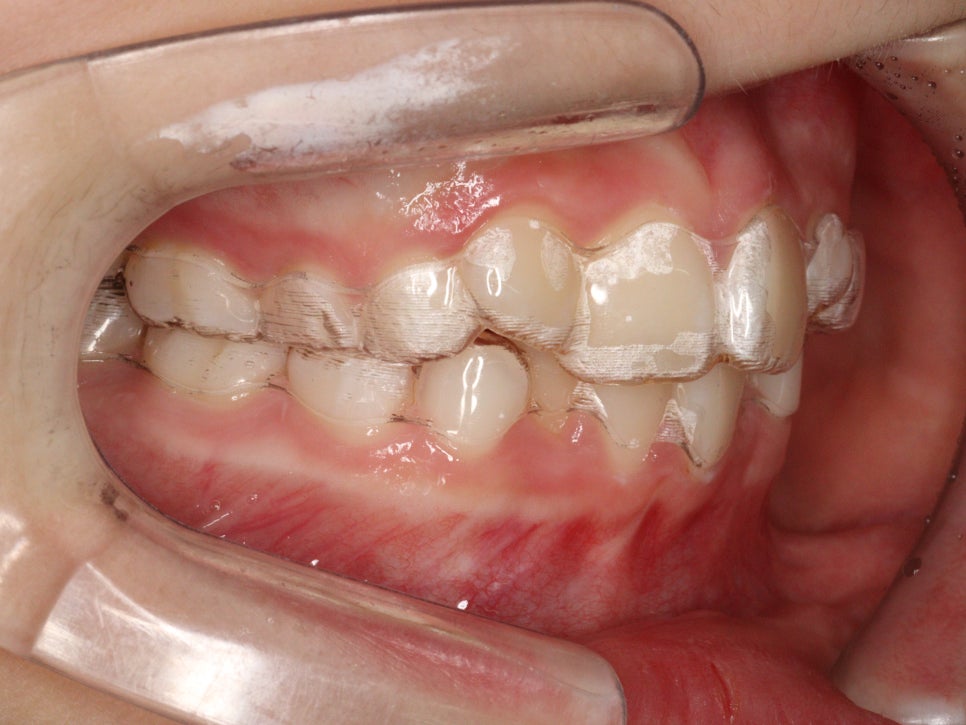

가장 기본이 되는 치료이니만큼 당연히 인비절라인보다 오래치료했고, 저희병원에도 인비절라인보다 더 많은 환자분들이 철사교정을 받고 있답니다.

아이들의 교정치료는 효율성 때문에 인비절라인을 조금 많이 하고 있습니다. 거의 대부분일지도.

하지만 대부분의 성인 환자분은 환자분의 의지에 의해 ‘인비절라인’과 장치’철사교정’ 을 선택하여 진행하게 됩니다.

성인 환자의 경우 환자의 의지에 따라 인비절라인과 철사교정 중 선택할 수 있습니다. 아이들의 교정치료는 효율성 때문에 인비절라인을 주로 사용하며, 특별한 케이스가 아닌 이상 대부분 인비절라인으로 진행됩니다.